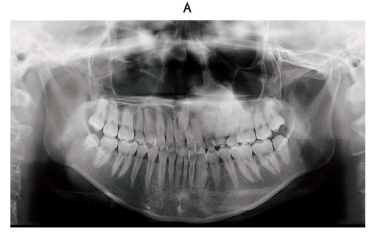

24 歳の女性。乳歯の残存を主訴として来院した。中学生のころから自覚し、矯正歯科治療を希望した際に精査を勧められたという。歯肉に異常所見はない。初診時のエックス線画像(別冊No. 27A)と CT(別冊No. 27B)を別に示す。

疑われるのはどれか。 1 つ選べ。

解答:c

解説:

パノラマ:左側の臼歯部根尖から上顎洞下部にかけてすりガラス状の不透過像

CT:左側上顎洞に埋伏歯と不透過像がみられる。

a 大理石骨病:もっと広がっているはず

b 骨形成線維腫:

c 線維性異形成症:すりガラス状!

d 慢性硬化性骨髄炎:骨髄炎は骨膜反応がみられる。

e セメント質骨性異形成症:多発性のことが多い